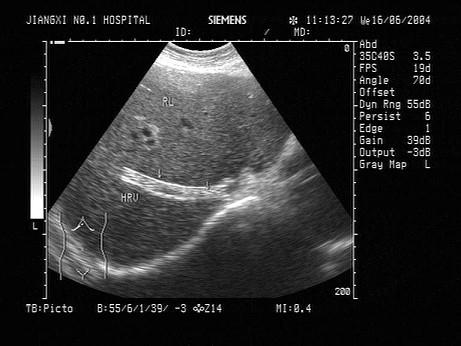

问题 一患者有介入手术史,具体病史不祥。肝脏超声检查声像图如下,图中箭头所示最可能的是?(?)

选项 A.支架 B.蛔虫 C.结石 D.正常结构 E.肝静脉

答案 A